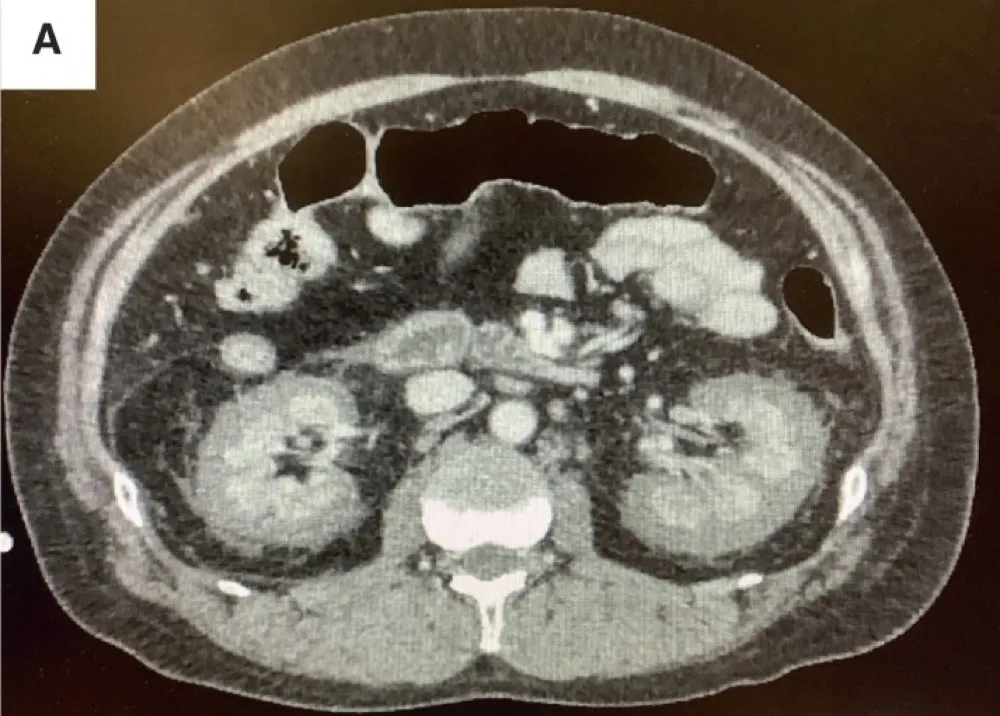

Hematuria e perda rápida da função renal em pacientes com câncer devem levantar suspeita de trombose da veia renal, mesmo sem contraste. Imagens não contrastadas e Doppler podem ser ferramentas-chave nesse contexto.

Febre e dor no flanco: pielonefrite ou infarto renal? Saiba como identificar os sinais radiológicos que fazem a diferença no diagnóstico e garantem o tratamento correto!

Descubra como o diagnóstico precoce da necrose cortical renal pode mudar o curso da lesão renal aguda em contextos críticos. Leia mais sobre este caso desafiador e suas implicações práticas para nefrologistas.

Frequentemente nos deparamos com pacientes que evoluem com quadro de IRA "desproporcional" ao quadro séptico, necrose cortical renal é uma entidade que não pode ser esquecida, principalmente em pacientes com complicações obstétricas